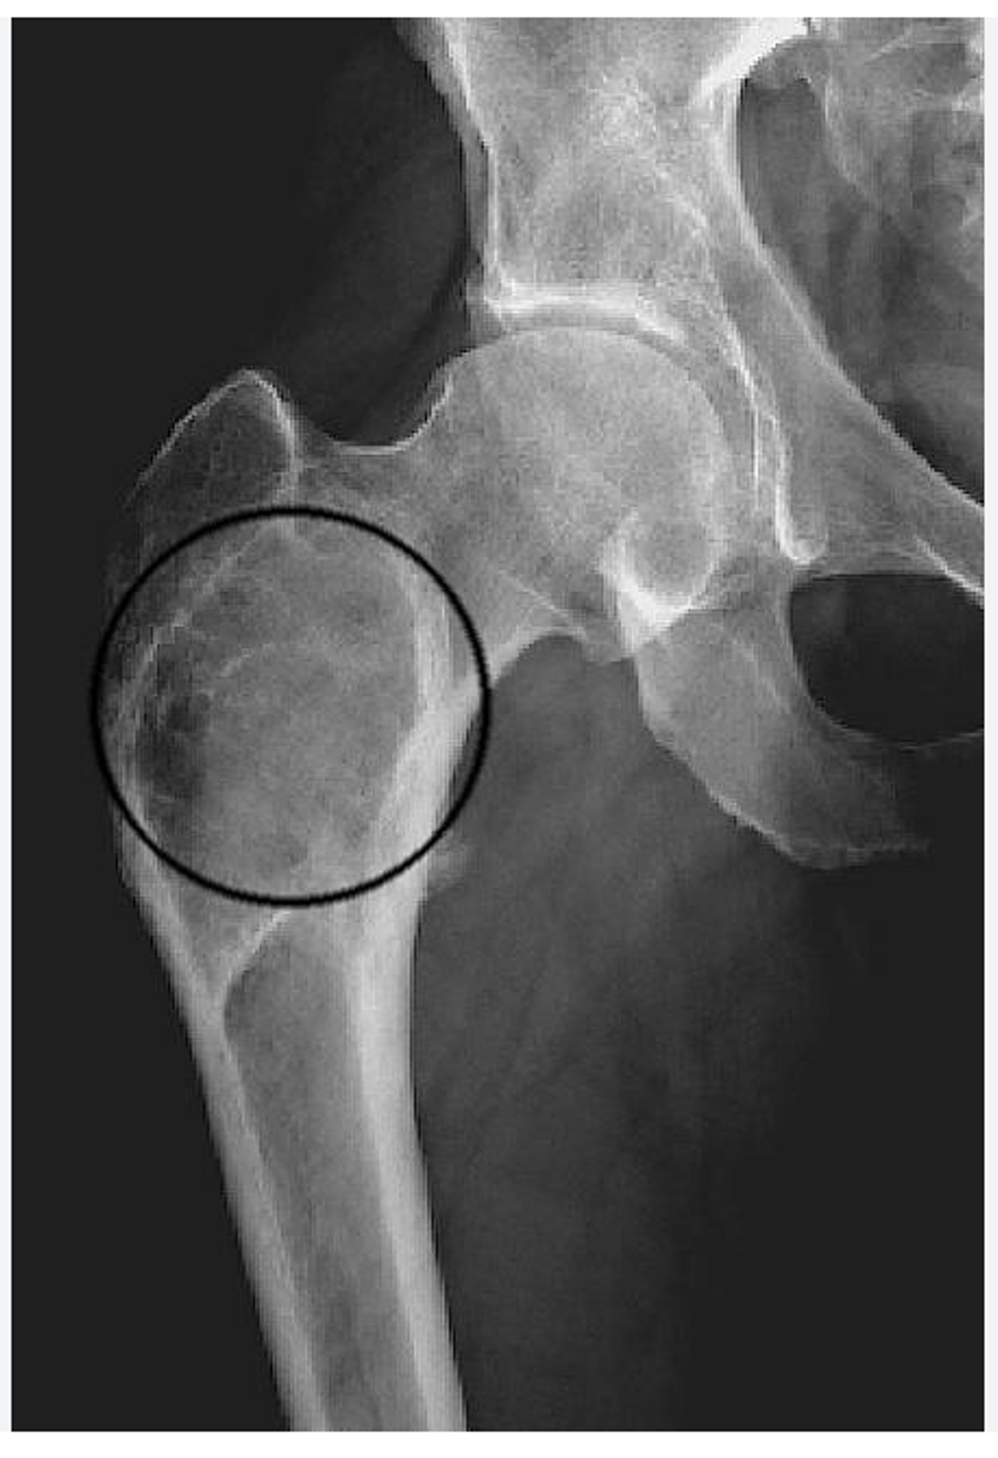

Where do secondary bone metastases tend to be found?

• in the central skeleton and proximal limbs (hips and shoulders)

Mechanism of long-bone metastasis…